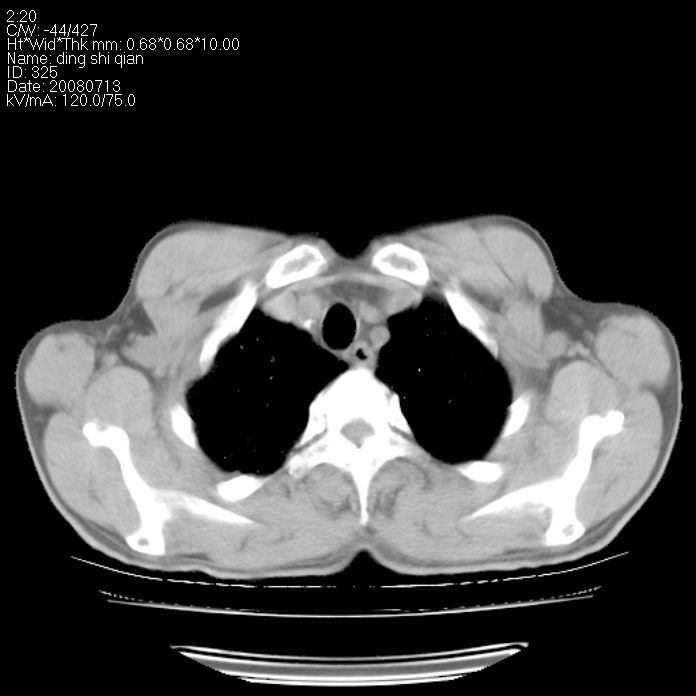

标题: CT14654:男 50岁 近来胸痛 [打印本页]

标题: CT14654:男 50岁 近来胸痛

右侧上肺块状软组织影,浅分叶,边缘毛刺证,与胸膜粘连,考虑:周围性肺癌

右侧上肺块状软组织影,浅分叶,边缘毛刺证,与胸膜粘连,考虑:周围性肺癌!支持!